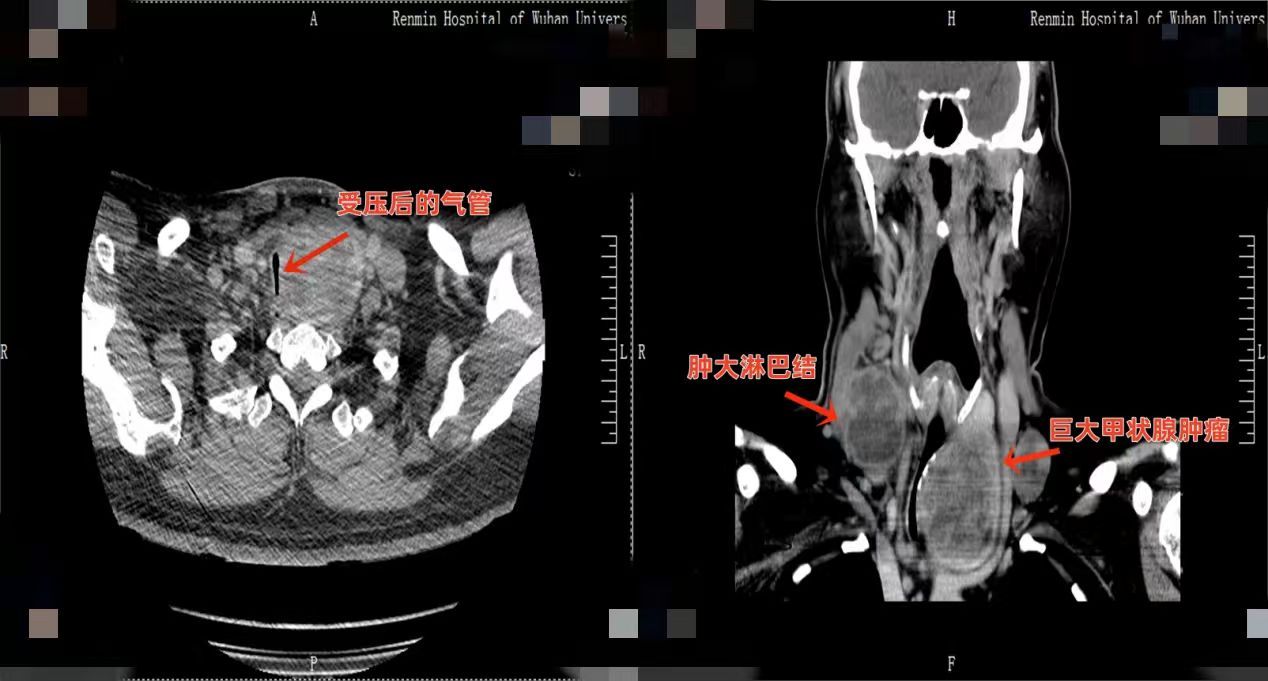

术前评估揭示重重风险:肿瘤与周边组织粘连紧密,气管最窄处仅剩4.5毫米;同时患者心功能极差,麻醉中随时可能出现心脏骤停。面对挑战,该院乳甲外科联合重症医学科、麻醉科、心血管内科等团队详细制定手术与应急预案。

手术当日,麻醉科夏中元教授、李维教授团队在纤支镜引导下,成功实施清醒气管插管,建立安全气道。随后,乳甲外科陈创教授团队为患者施行甲状腺全切及淋巴结清扫术。术中,医生在紊乱的解剖结构中精细分离,成功将巨大肿瘤完整切除,并保护了喉返神经、甲状旁腺等重要结构。术后病理显示为甲状腺癌。